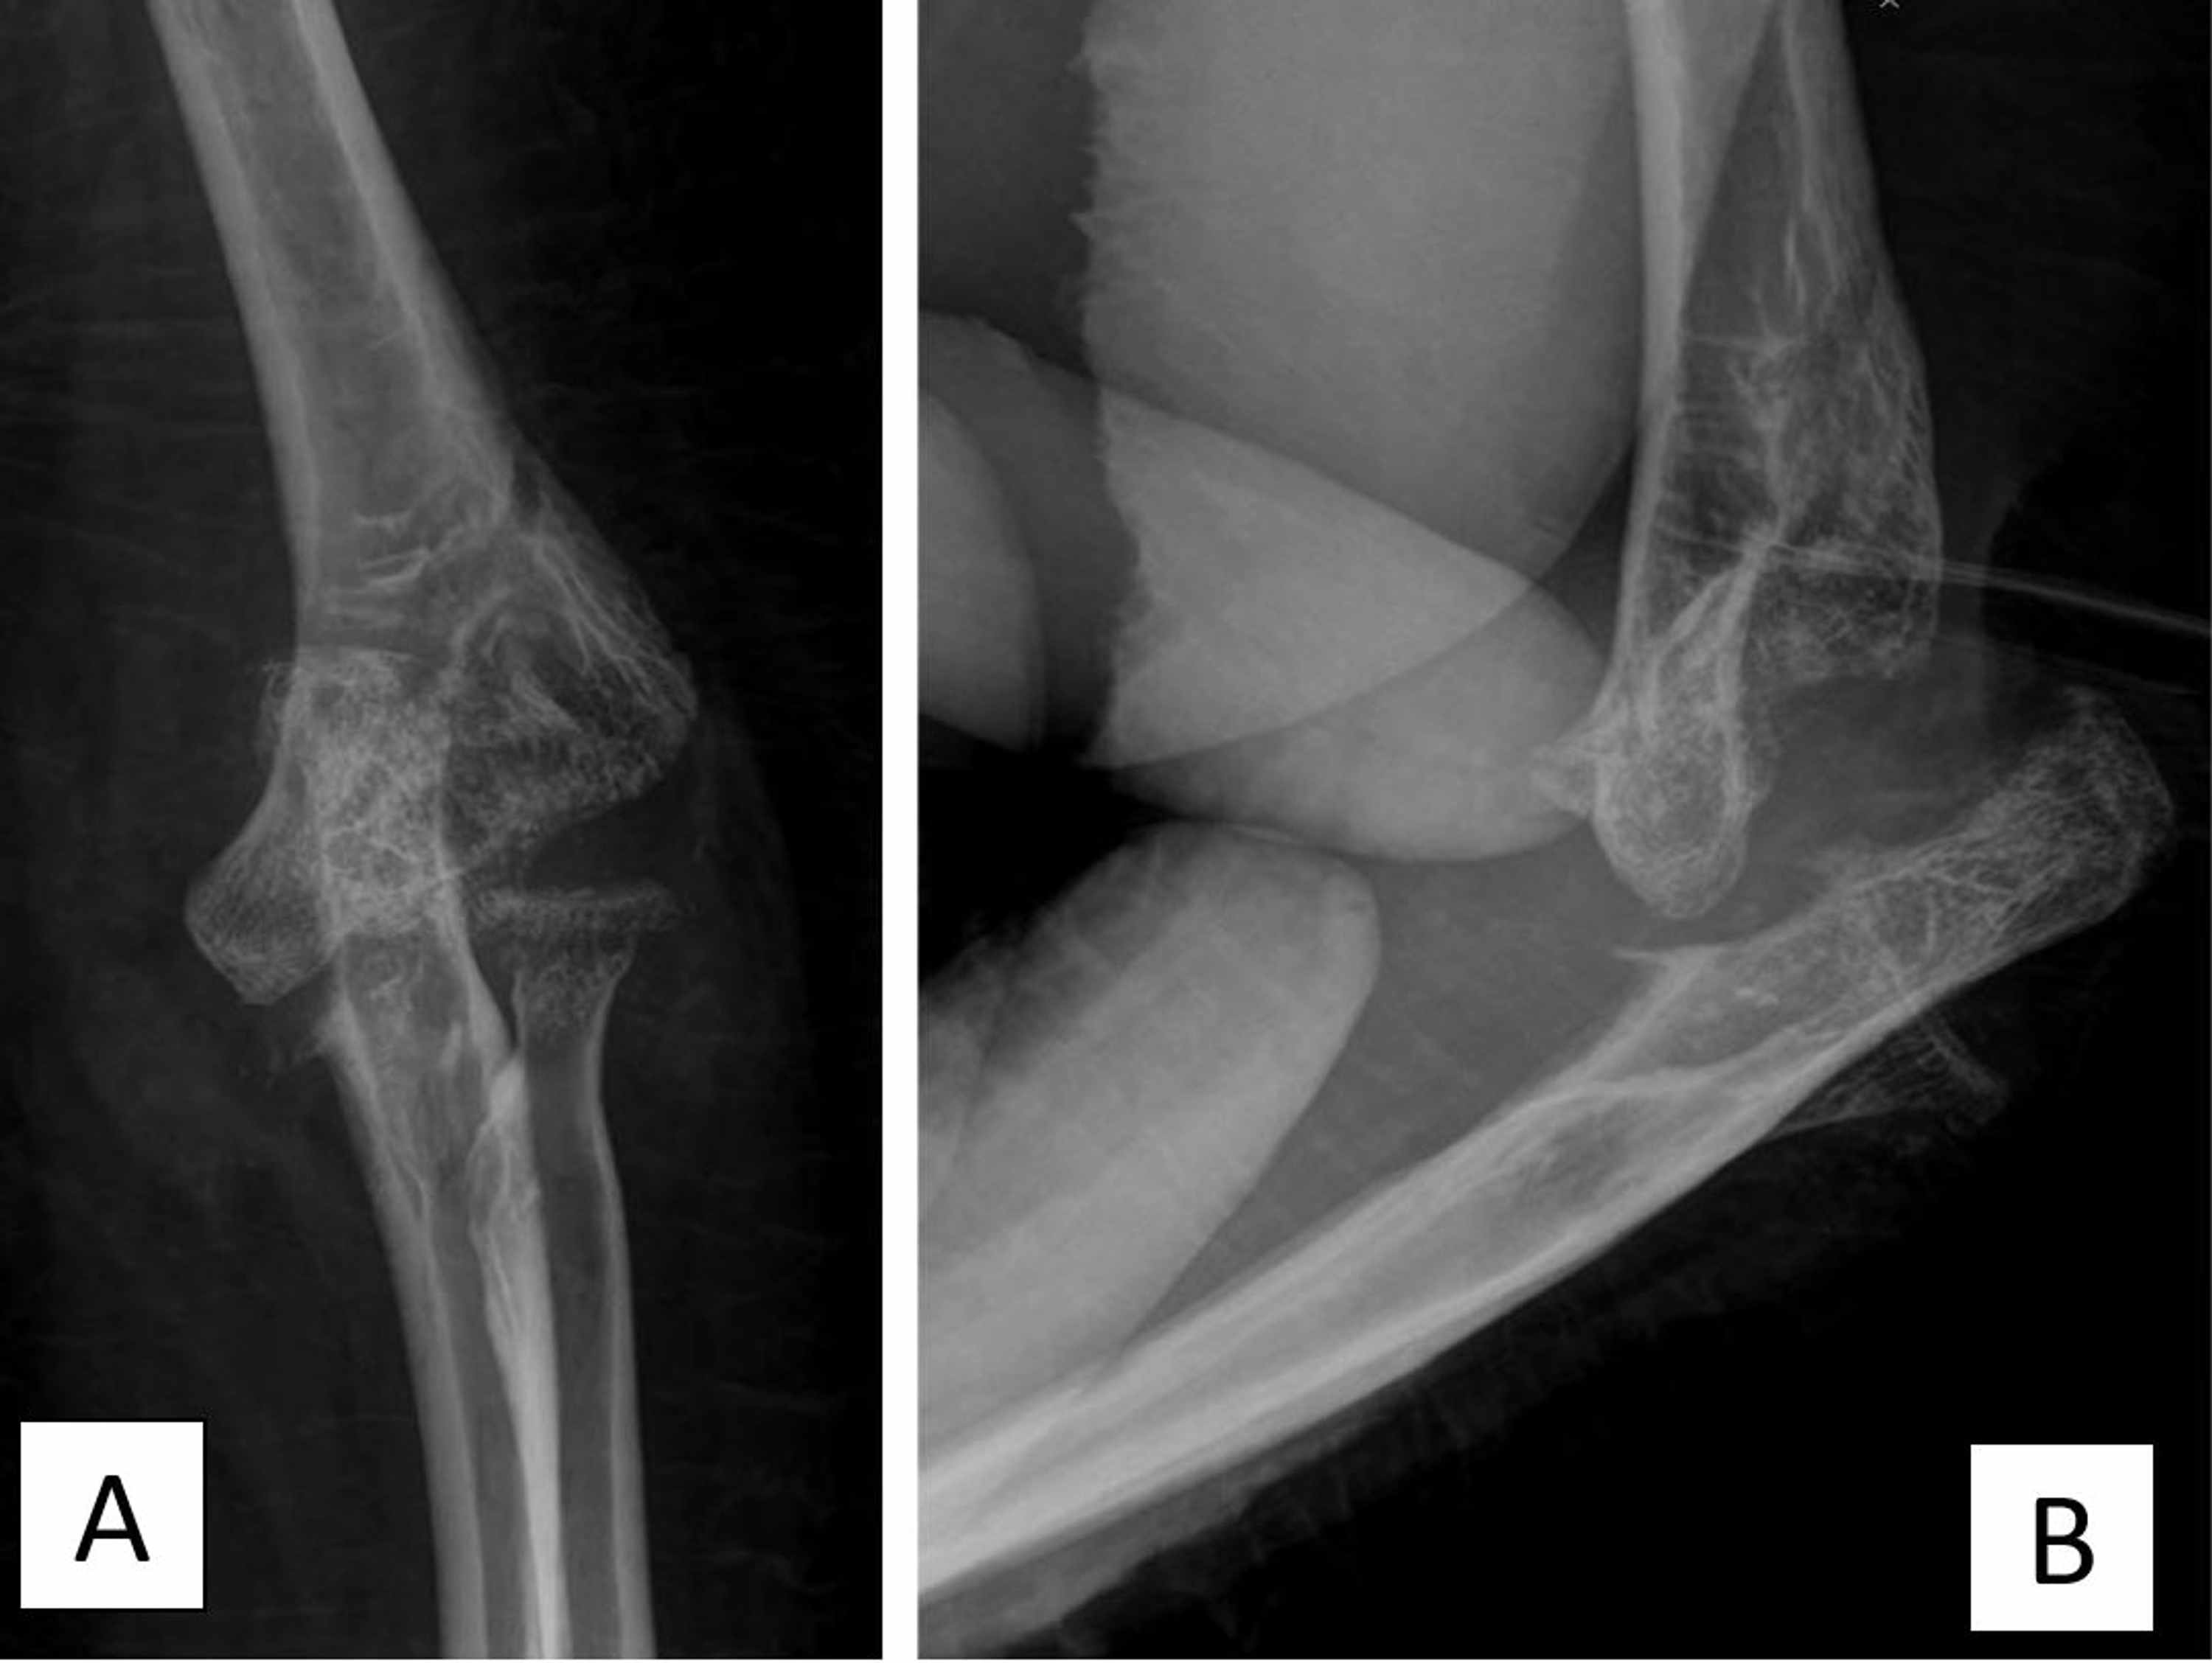

Previous septic arthritis Radiology at St. Vincent's University Hospital Septic Arthritis Elbow X Ray Septic arthritis of the shoulder and elbow primarily affects individuals with clinical comorbidities and/or those who are. The differential diagnosis of an acutely painful joint is broad and includes crystalline and inflammatory. The epidemiology, microbiology, clinical manifestations, diagnosis, differential diagnosis, and treatment of septic arthritis of. Oligoarticular septic arthritis is more likely to present with symptoms of systemic infection and. Septic Arthritis Elbow X Ray.